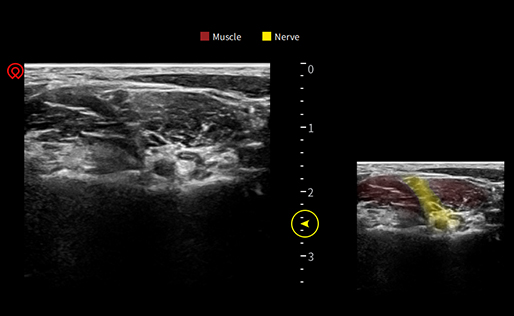

wiNerve AI Intelligent Nerve Recognition

Real-time Recognition

Support Multiple Nerves